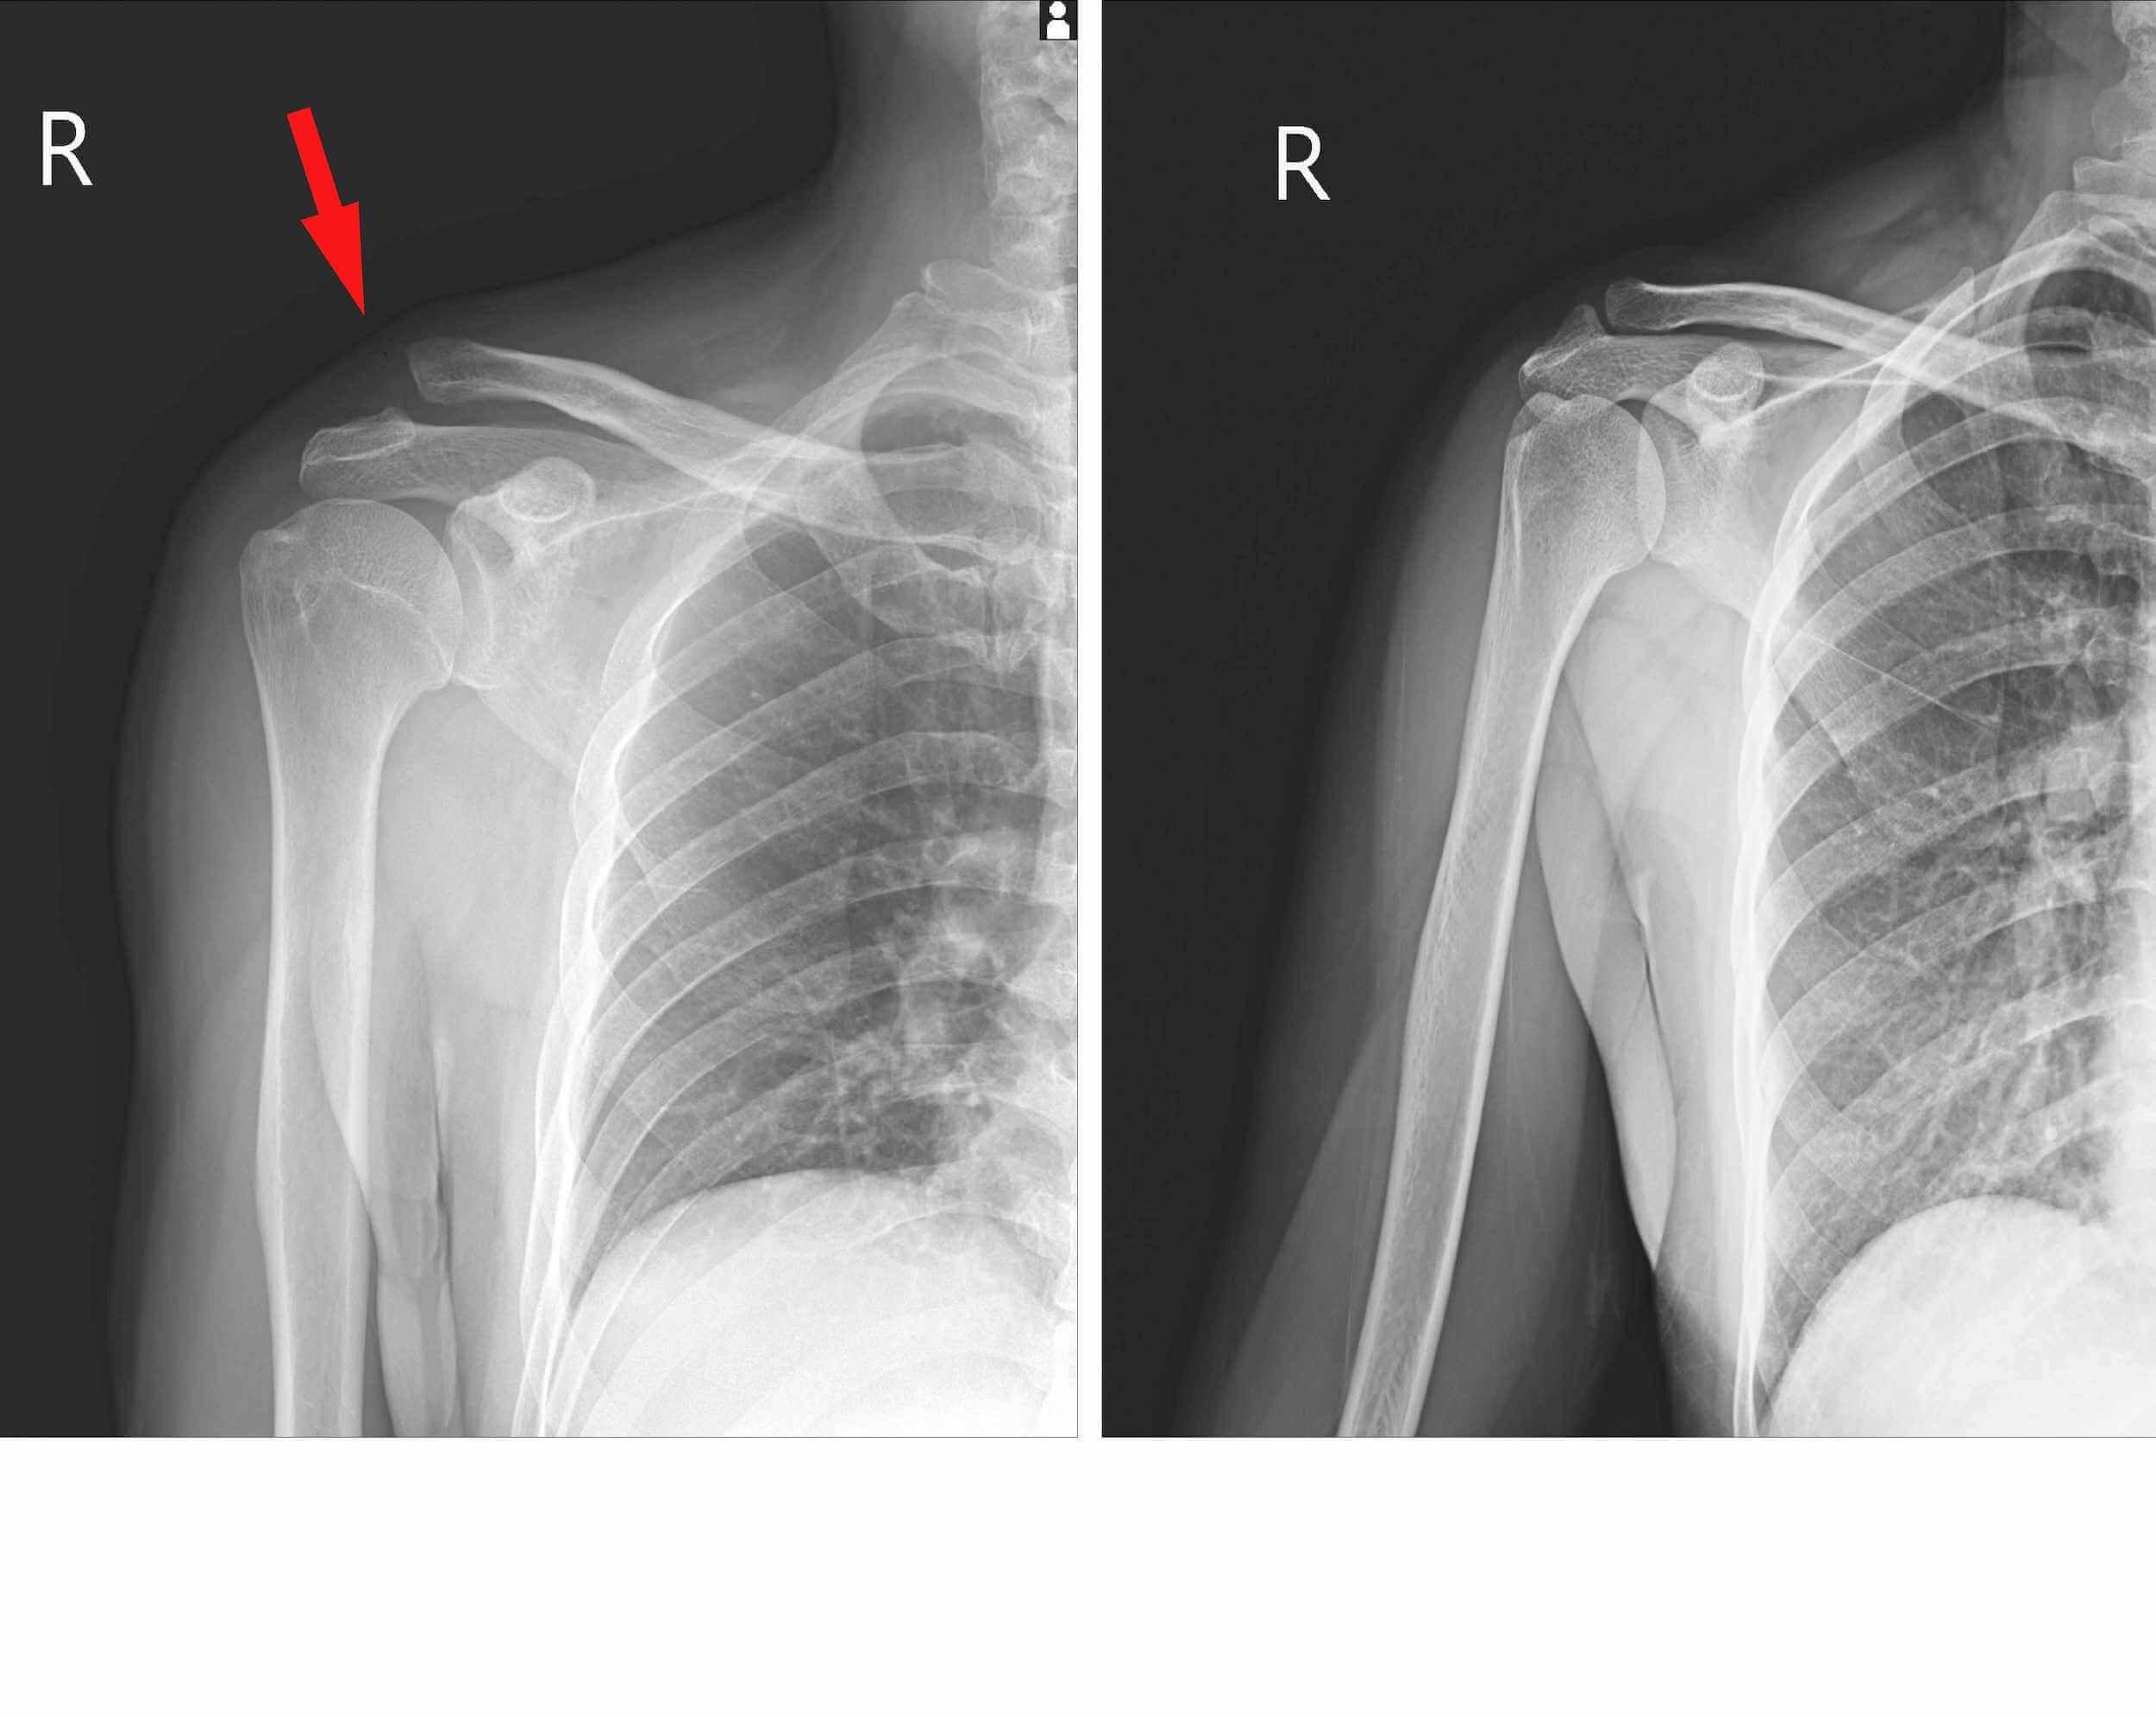

Zanesljiva diagnostična metoda za pregled rame, kjer obstaja sum na kalcinacije je ultrazvočna preiskava (UZ) pri specialistu radiologu. Z ultrazvočnim slikanjem se natančo določi lokacijo kalcijevih kristalov in njihovo velikost, lahko pa se uporablja tudi kot metoda spremljanja napredka konzervativnega zdravljenja kalcinacije rame.